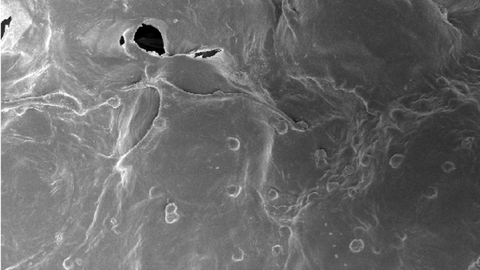

Por iso, un proxecto con investigadores do CSIC está a estudar o desenvolvemento de cápsulas biolóxicas nas que se albergarán estas células CAR-T coas que tratar de forma específica este tipo de tumores sólidos. Nel participan o Centro de Investigación contra o Cancro de Salamanca (CIC, un instituto mixto de investigación do CSIC e a Universidade de Salamanca), o Centro de Investigación Biomédica en Rede de Cancro (CIBERONC), a Universidade de Santiago de Compostela (USC), o Centro de Fabricación de Terapias Avanzadas de Galicia (GALARIA), e o CIMA Universidade de Navarra.

José Rivas Rey, coordinador do proxecto e catedrático do Departamento de Física Aplicada da Universidade de Santiago de Compostela, confesa que o principal reto deste proxecto, que finaliza este ano, foi «que esas células CAR-T liberásense e mantivesen vivas e activas na cápsula durante tempos prolongados». Para entendelo mellor, detalla que, primeiro, elaboraron as cápsulas cun polímero natural que «funciona como un colector de dous ou tres milímetros dentro das cales van embebidas as células CAR-T cun cóctel de moléculas bioactivas que as mantén vivas e activas». As células multiplícanse dentro das cápsulas e «poden saír durante máis de vinte días, o que permite o seu uso localizado dentro do tumor durante tempos prolongados».

A boa noticia, remarca Rivas, é que os resultados son positivos. «Fixemos un estudo in vivo, con resultados moi positivos. Estamos moi contentos porque os tumores se reduciron, necesitándose para iso números de células CAR-T moi inferiores a cando estas se administran no torrente circulatorio como é habitual». Aínda que, opta pola prudencia: «Que funcione neste ámbito, ata chegar á clínica, falta un gran paso». Do mesmo xeito que Troia non se conquistou nun ano, estas biocápsulas con células CAR-T tamén necesitan tempo para acabar cos tumores sólidos. «En dous ou tres meses remataremos este proxecto no que levamos tres anos e os resultados son prometedores, pero aínda quedan moitos controis e maduración», comenta Rivas.

Xosé Bustelo tamén é un dos investigadores principais deste proxecto. «Creo que o interesante deste desenvolvemento, que ata o de agora é soamente preclínico, é permitirnos levar directamente as células CAR-T de forma activa ao tumor sólido sen que estas se dispersen por todo o organismo, senón que xustamente queden alí onde son necesarias para a súa función. Co cal, temos máis soldados no campo de batalla que se utilizamos CAR-T "normais". Outro punto importante é que ese «biocóctel» que se atopa nestas cápsulas ten un ámbito de acción local, «o que evita efectos secundarios negativos como é a indución de reaccións inflamatorias a nivel de organismo», conclúe.